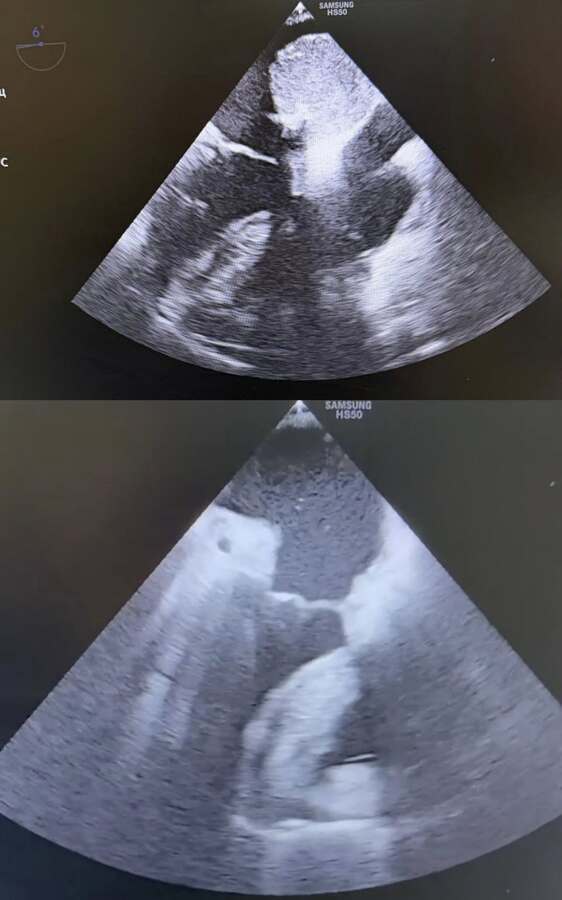

Під час обстеження у пацієнтки виявили міксому лівого передсердя. Це доброякісне, проте надзвичайно підступне новоутворення. Пухлина була рухливою та зміщувалася синхронно з кожним ударом серця. Такий стан створював подвійну смертельну небезпеку. З одного боку, міксома могла будь-якої миті перекрити клапанний отвір, спричинивши раптову зупинку кровообігу. З іншого — існував високий ризик відриву фрагментів пухлини, що призвело б до емболії та важких судинних катастроф.

Зволікати було неможливо, тому лікарі прийняли рішення про невідкладне хірургічне втручання. Операція відбувалася в умовах штучного кровообігу. Кардіохірурги виконали розтин передсердя та провели радикальне видалення пухлини. Завдяки професіоналізму команди вдалося повністю відновити внутрішньосерцеву анатомію та стабілізувати гемодинаміку.